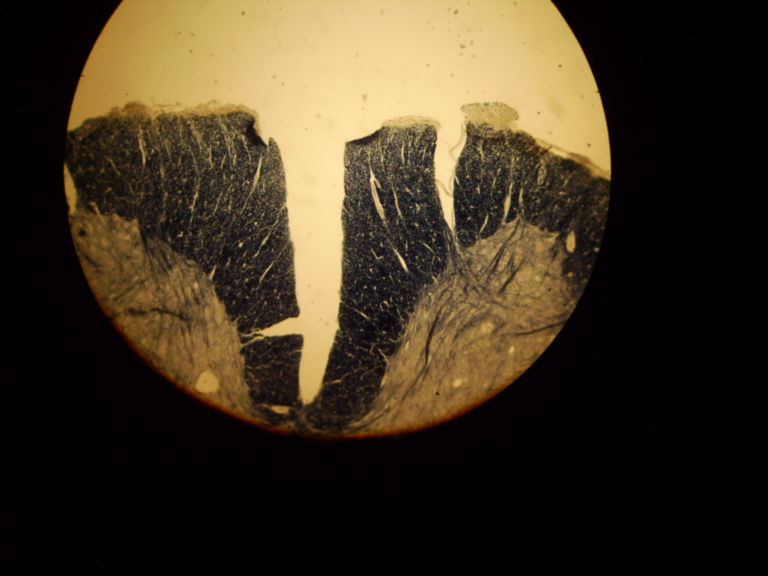

From www.wikiskripta.eu

Tabes dorsalis (preparát) WikiSkripta Tabes Dorsalis Oq E tabes dorsalis é uma complicação desta infecção que danifica os tecidos da medula espinhal, resultando em diminuição da função dos músculos com fraqueza progressiva das extremidades superiores e inferiores. tabes dorsal (ataxia locomotora) envolve degeneração lenta e progressiva do corno posterior e das raízes nervosas. Tardiamente, ocorrem perda da sensibilidade vibratória e propriocepção, além de arreflexia. A medula. Tabes Dorsalis Oq E.

Tabes dorsalis (preparát) WikiSkripta Tabes Dorsalis Oq E tabes dorsalis é uma complicação desta infecção que danifica os tecidos da medula espinhal, resultando em diminuição da função dos músculos com fraqueza progressiva das extremidades superiores e inferiores. tabes dorsal (ataxia locomotora) envolve degeneração lenta e progressiva do corno posterior e das raízes nervosas. Ela normalmente se desenvolve vinte a trinta. A medula espinhal se deteriora progressivamente.. Tabes Dorsalis Oq E.